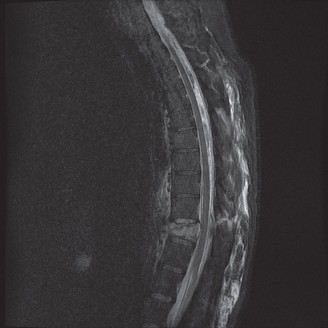

When surgical intervention becomes unavoidable, meticulous pre-operative planning is the cornerstone of a successful outcome. Advanced imaging is non-negotiable. An MRI with and without gadolinium contrast is the gold standard for defining the extent of the epidural abscess, the degree of neural compression, and the involvement of adjacent paraspinal musculature (e.g., psoas abscess). T1-weighted images typically show hypointense signals in the infected marrow, while T2-weighted and STIR sequences reveal hyperintense fluid and edema in the disc space and vertebral bodies. Gadolinium enhancement highlights the vascularized inflammatory phlegmon and the capsule of any abscesses.

In addition to MRI, a fine-cut computed tomography (CT) scan is essential for evaluating bony destruction. CT allows the surgeon to assess bone stock for pedicle screw purchase and to template the size of the interbody cages required for anterior column reconstruction. Upright standing radiographs (if the patient can tolerate them) or full-length supine films are necessary to evaluate global spinal alignment and regional kyphosis.